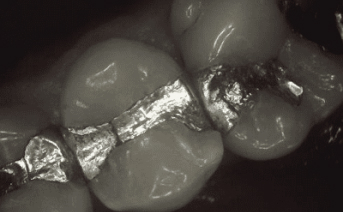

Our composite dental fillings in Atlanta, Georgia, not only fill in cavities, but can treat various cosmetic treatments by filling in teeth that have been damaged or demineralized. Schedule your treatment at Smiles of Atlanta with our dentist, to see if you need a composite dental filling from Dr. Ed Trizzino. Call 770-777-0808 today.